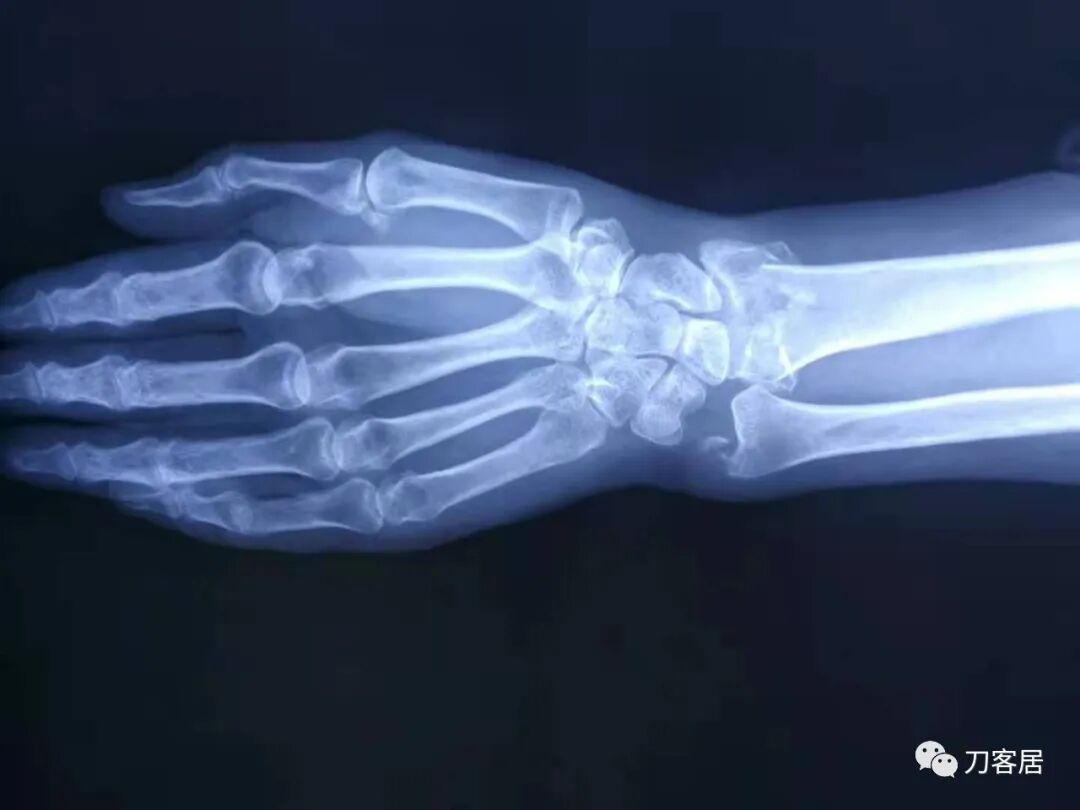

2021年7月22日晚,上海美华医院儿童骨科的师东良医生,给我提供了一例他处理的严重移位尺桡骨双骨折病例,经过手法复位,石膏外固定治愈。这个病例,其他医院建议要做手术。实际上,这样的病例,在现实中有太多太多,因为手法复位,石膏外固定治疗骨折,这是骨科医生的基本功。

超声引导下闭合手法复位石膏外固定治疗7岁患儿尺桡骨远端移位双骨折。

男,7岁,左前臂远端桡尺骨双骨折,术前X光片见图1,行超声引导下闭合复位石膏外固定术,康复训练,6周拆石膏,随访2.5月的效果。术后2.5X光片见图23。功能上仅前臂旋后较健侧减小15°,继续加强康复训练中。家长满意,评价见图4

1. 超声引导下闭合复位石膏外固定术左尺桡骨双骨折